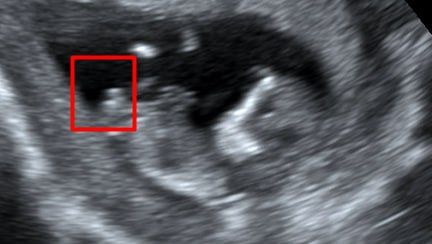

Скриншот с видео ⬆️

Буду мамой дочки

Такой же был - девочка 🤭

Вот, муж еще скидывал, искал пысун, потому что врач на первом скрининге предположила мальчика)